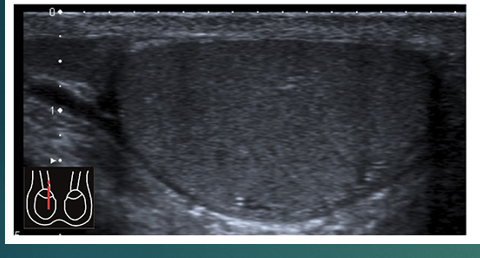

List caudal, cranial, anterior and posterior

list the 2 pieces of anatomy

what do you see